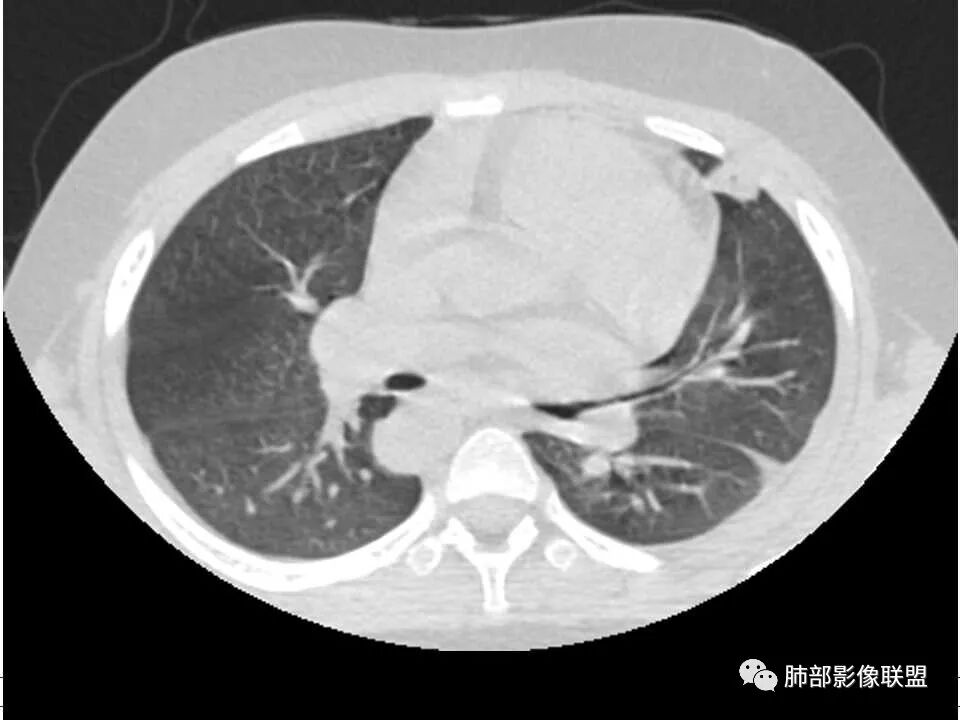

患者儿童,因右下肢疼痛伴肿胀14天就诊。病程中有发热及伴随症状。膝关节MRI提示右侧膝关节及右髌骨髁异常信号影,右膝髌上囊及关节腔内少量积液。胸部CT:双肺胸膜下多发结节影,部分结节空洞形成,且结节周围可见血管集束征。综合考虑血源性脓毒性肺栓塞、坏死性肺炎。右侧骨髓炎、血播性金葡菌肺炎,鉴别其他特殊感染及血管炎。

胸部ct:双肺多发空洞,结节,外带下叶为主,空洞内外光滑,有血管滋养征,综合病史及影像考虑脓毒性肺栓塞,结合病史,金葡可能性大。

小儿,急性起病,下肢疼痛,mr提示骨髓水肿,临床化验炎性指标高,考虑金葡菌骨髓炎,双肺多发结节,以血管支气管束及胸膜下分布为主,部分结节近端与血管相连,部分结节可见空腔,内壁光整,部分囊腔有张力,考虑骨髓炎并肺内血播感染,金葡?

2.双肺多发片影,随机分布,多空洞或囊腔,胸膜下多楔形影,气道未见受累等等符合脓毒血症影像学表现,尤其是金葡。